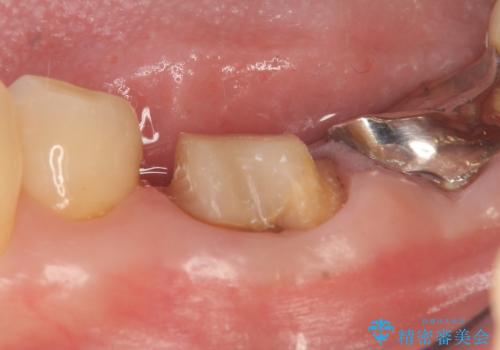

- 左下の銀歯が外れたので診て欲しいといらっしゃった方の症例です。

他院にて再装着したが不安なので、根管治療からやり直したいとのことでした。

再根管治療終了後、オールセラミッククラウンによる補綴を行いました。